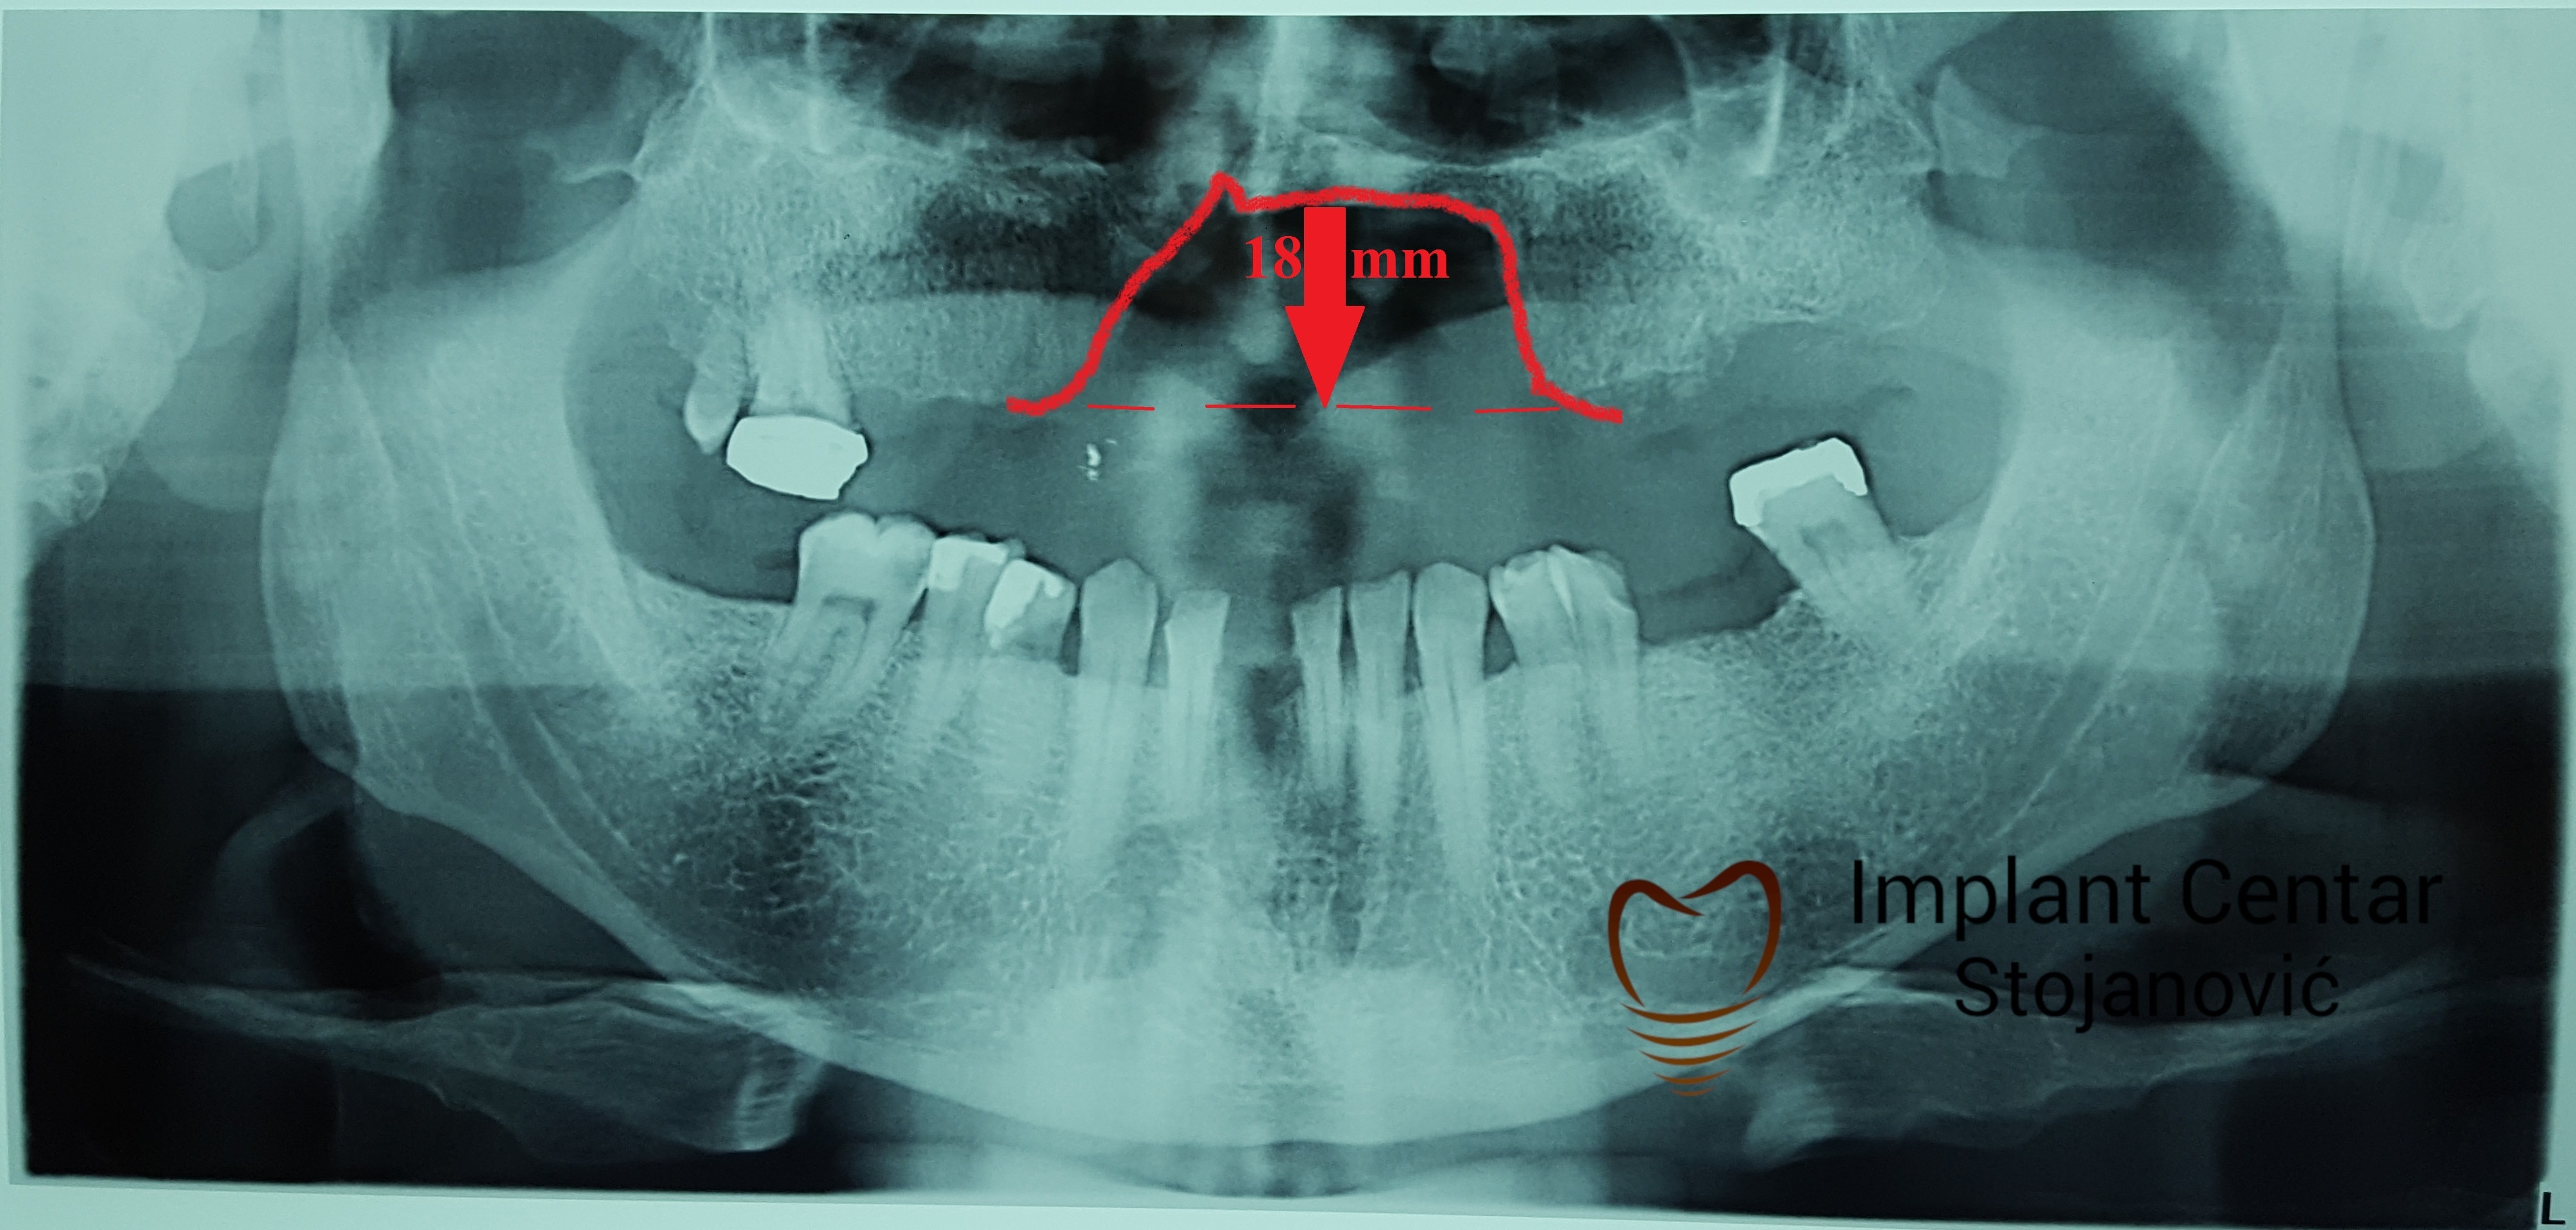

Implantno-protetska sanacija defekta gornje vilice uzrokovanog ratnom traumom

Pacijent iz USA sa ratnom traumom zadobijenom tokom rata u BiH Dum-Dum metkom.

PRISTUPILI SMO RESAVANJU DEFEKTA GORNJE VILICE SA CILJEM MAKSIMALNOG KOMFORA I SIGURNOSTI ZA PACIJENTA UGRADNJOM IMPLANTATA I IZRADOM FIKSNOG METALOKERAMICKOG MOSTA